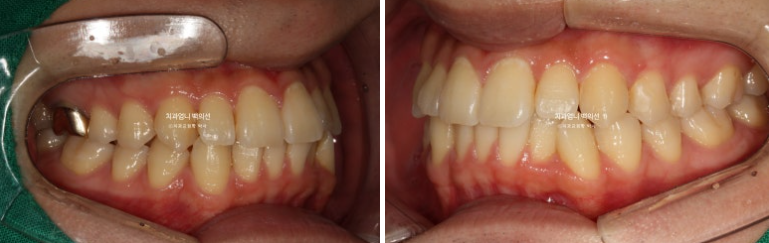

24.09

앞니 중심선 불일치가 많이 좋아졌으나 아직 완벽히 맞지는 않습니다.

어금니 교합도 교합관계 자체는 1급으로 좋아졌으나 위아래 틈이 보입니다.

22.10~25.03

앞니뻗침이 개선되었습니다.

앞니 뻗침과 돌출이 위 아래 각각 2mm 가량 개선된 것이 보입니다.